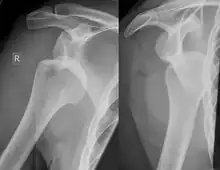

Anterior shoulder dislocation on X-ray with a large Hill–Sachs lesion

X-ray at left shows anterior dislocation in a young man after trying to get up from his bed. X-ray at right shows same shoulder after reduction and internal rotation, revealing both a Bankart lesion and a Hill-Sachs lesion.